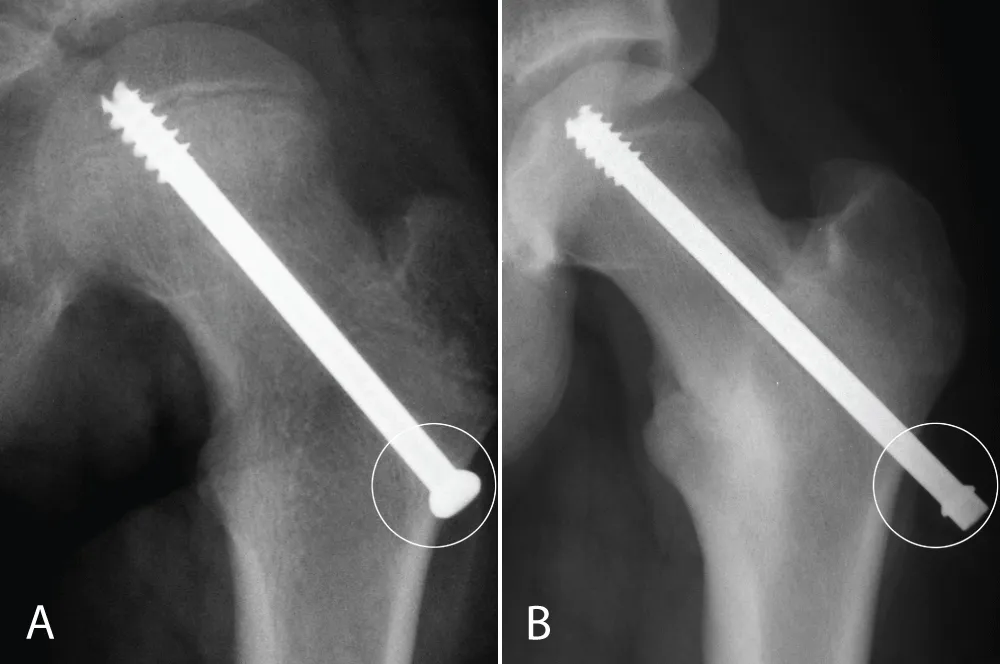

Approval from the Institutional Review Board was obtained before initiating this retrospective study. Between 1990 and 2002, patients with unilateral SCFE who had screw fixation and complete radiographs were included. Patients with atypical SCFE were excluded. Radiographs were assessed for physeal closure, and the time from the primary surgery until physeal closure was calculated. Closure was defined as 80% or more obliteration of the physis on both the anterior-posterior and lateral view [6]. The date of the first radiograph showing closure was set as the date of closure. If the time interval between the radiograph showing closure and the previous radiograph exceeded 6 months, patients were excluded since the date for closure in these patients was uncertain. Data regarding age, gender, degree of slip, and whether the triradiate cartilage was open or closed were collected. The position of the screw was assessed, and it was noted if the threads of the screw were crossing the physis or were contained entirely within the epiphysis (Figure 1A and B). In addition, the position of the screw head in relation to the lateral cortex was assessed. It was noted if the screw head was flush with the lateral cortex (≤ 5 mm exposure) or left proud (Figure 2A and B). Two orthopedic surgeons who were not involved in the care of any of the patients performed the radiograph assessments.

Figure 2: A and B: The screw head is flush with the lateral cortex, and (2B) the screw head is left proud more than 5 mm.